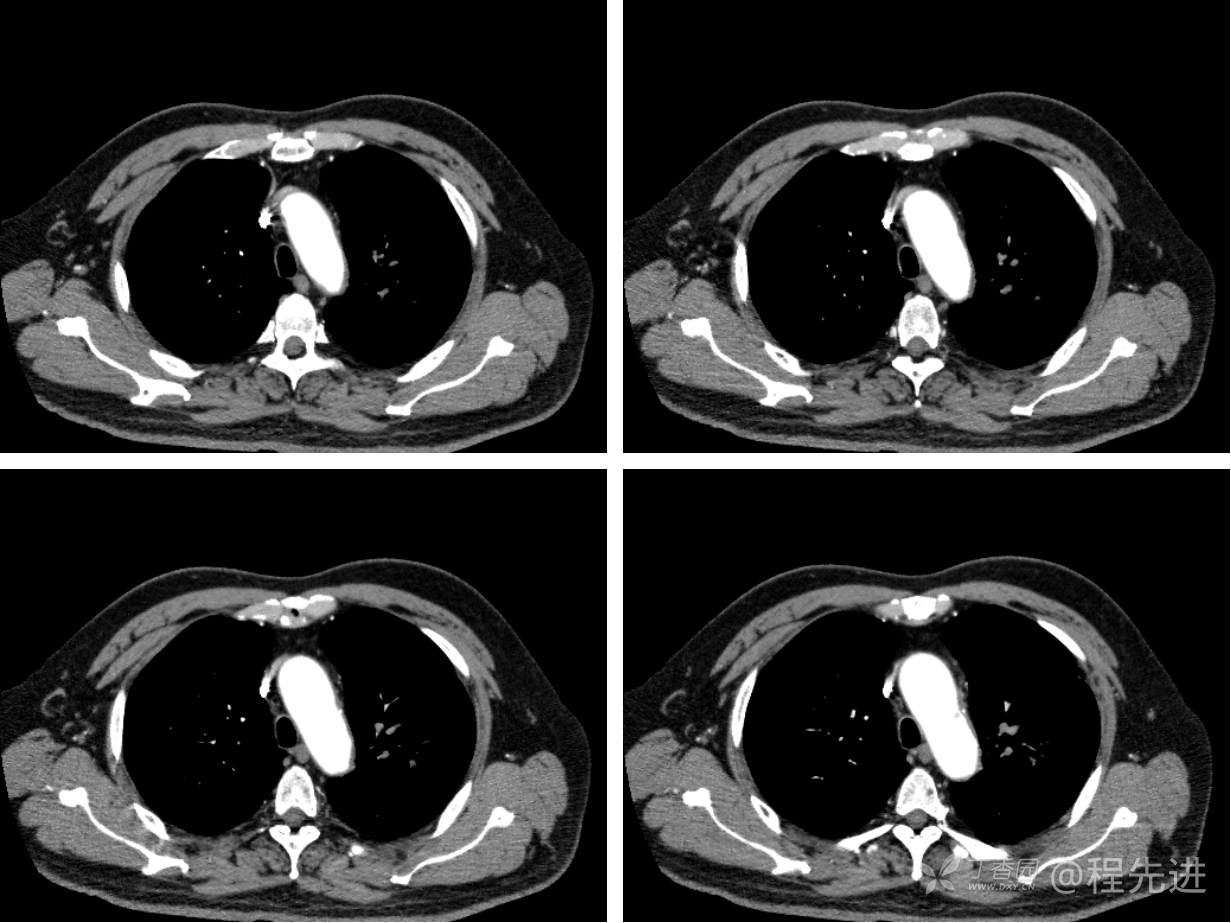

现病史概要:患者入院前约半月无明显诱因下出现咳嗽、胸闷症状,无明显发热症状,咳少量白痰,无明显咯血、喘息、头晕等不适,就诊我院查胸部CT示上纵膈肿物,左肺上叶支气管内肿物,现为行进一步治疗收入胸外科,患者近来饮食睡眠尚可,二便如常。